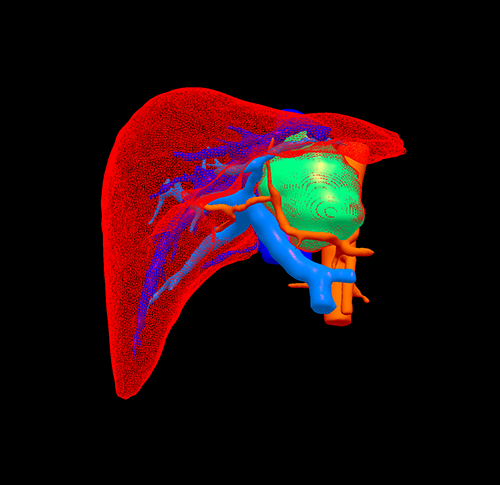

尾状叶肿瘤--尾状叶切除